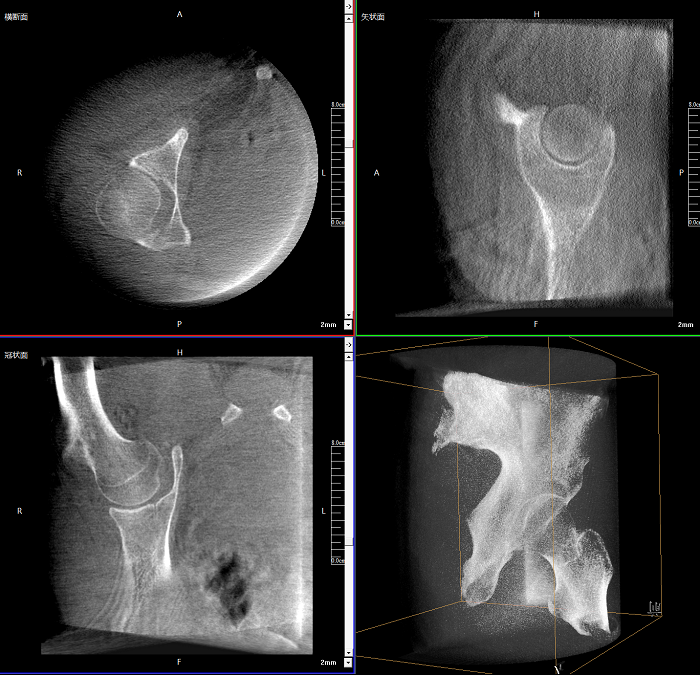

三維成像 全面觀(guān)察

任意視角、任意切面觀(guān)察

術(shù)中實(shí)時(shí)生成橫斷面、矢狀面、冠狀面及三維影像,可在任意切面、任意角度評估植入物和解剖結構的相對位置。

術(shù)中CT檢查 減少翻修概率

通過(guò)術(shù)中三維影像的檢查,可以立即發(fā)現植入物的錯位,減少不必要的第二次手術(shù),減少并發(fā)癥概率以及感染風(fēng)險。